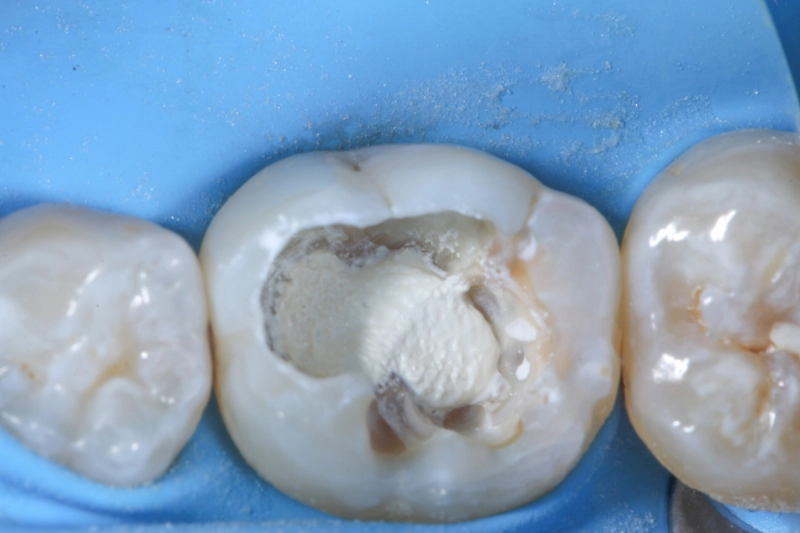

1-Stift-Technik Step by Step

- Step 1: Vorbereiten: Der Wurzelkanal wird mit entsprechenden Instrumenten aufbereitet.

- Step 2: Trocknung des Kanals mit formkongruenten Papierspitzen

- Step 3: Wurzelkanalsystem wird mit Sealer (KometBioSeal) aufgefüllt

- Step 4: Guttaperchastift in pumpenden Bewegungen auf Arbeitslänge einbringen und bspw. mit dem DownPack auf Höhe des Pulpakammerbodens kürzen.